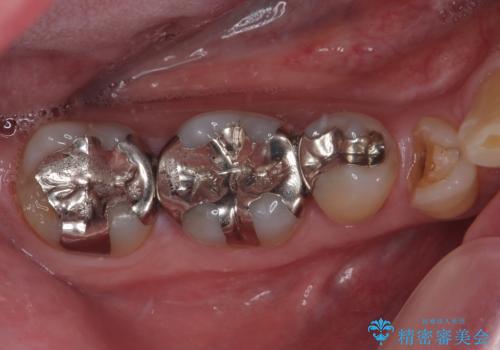

銀歯の下の虫歯を治したい オールセラミッククラウン・セラミックインレー修復

銀歯をセラミックにしたい オールセラミッククラウン

銀歯を外したい オールセラミッククラウン

右下の銀歯が外れた オールセラミッククラウン